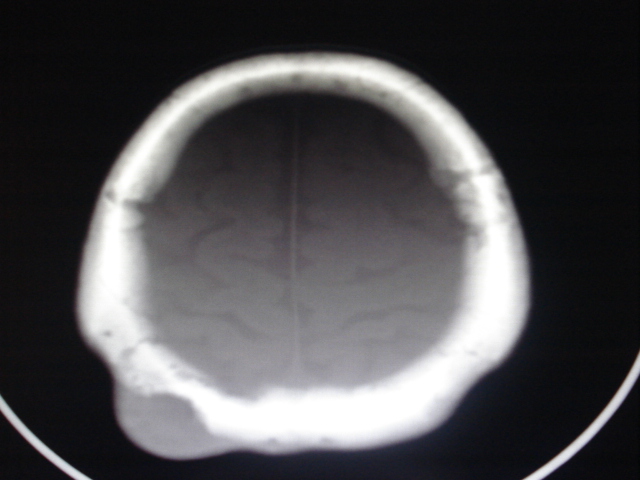

骨质破坏+软组织肿块+好发部位  支持骨嗜酸性肉芽肿。

可以考虑为骨嗜酸性肉芽肿,但是必须和骨髓炎、结核、孤立性骨囊肿、纤维异样增殖症和一些恶性骨肿瘤相鉴别。故应作活组织检查以确诊。

年纪太大,单发,有明确软组织肿块,不考虑为骨嗜酸性肉芽肿。表皮样囊肿可能性大

年龄大,无“纽扣样”死骨,软组织肿块密度较低且边界清楚,由内板向外破坏,不支持嗜酸性肉芽肿。

考虑转移瘤、表皮样囊肿、骨纤、板障型脑膜瘤、颅骨淋巴瘤鉴别。

倾向于板障型脑膜瘤,淋巴瘤待排除,建议增强及mri进一步检查。